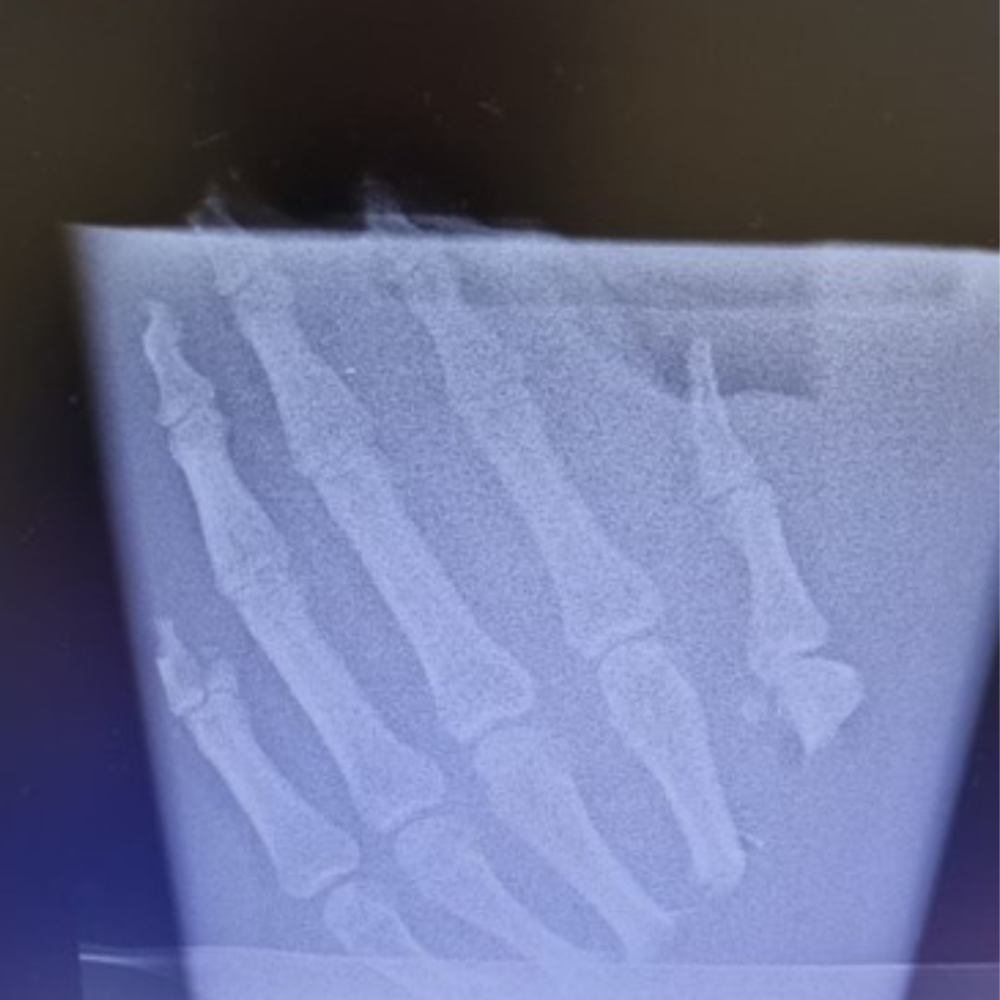

W ciągu prawie 2 lat działalności, oprócz regularnych dyżurów, wykonano również ponad 10 replantacji poza grafikiem. Jest to o tyle szczególna sytuacja, że do zabiegu znaczna część personelu przyjeżdża z domu w swoim wolnym czasie, po to, by pomóc uniknąć pacjentowi ciężkiego kalectwa po amputacji. Takie „pospolite ruszenie” zdarza się głównie wtedy gdy w grafiku „serwisu” nie ma zgłoszonego ośrodka lub pacjentów po urazie amputacji w danym dniu jest więcej niż ośrodków, które dyżurują. Do najczęściej przeprowadzanych zabiegów w ciągu roku działalności 5WSzKzP w „serwisie replantacyjnym” należały: replantacje palców  (głównie kciuka), rewaskularyzacje (niepełne amputacje ale wymagające pilnego szycia naczyń) oraz ciężkie wielotkankowe urazy ręki. W trakcie prawie 2 letniej działalności wykonano około 50 takich procedur.